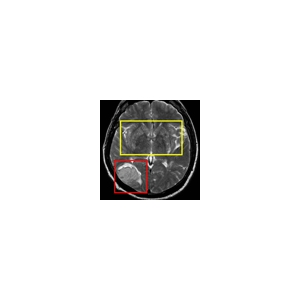

Bildergalerie